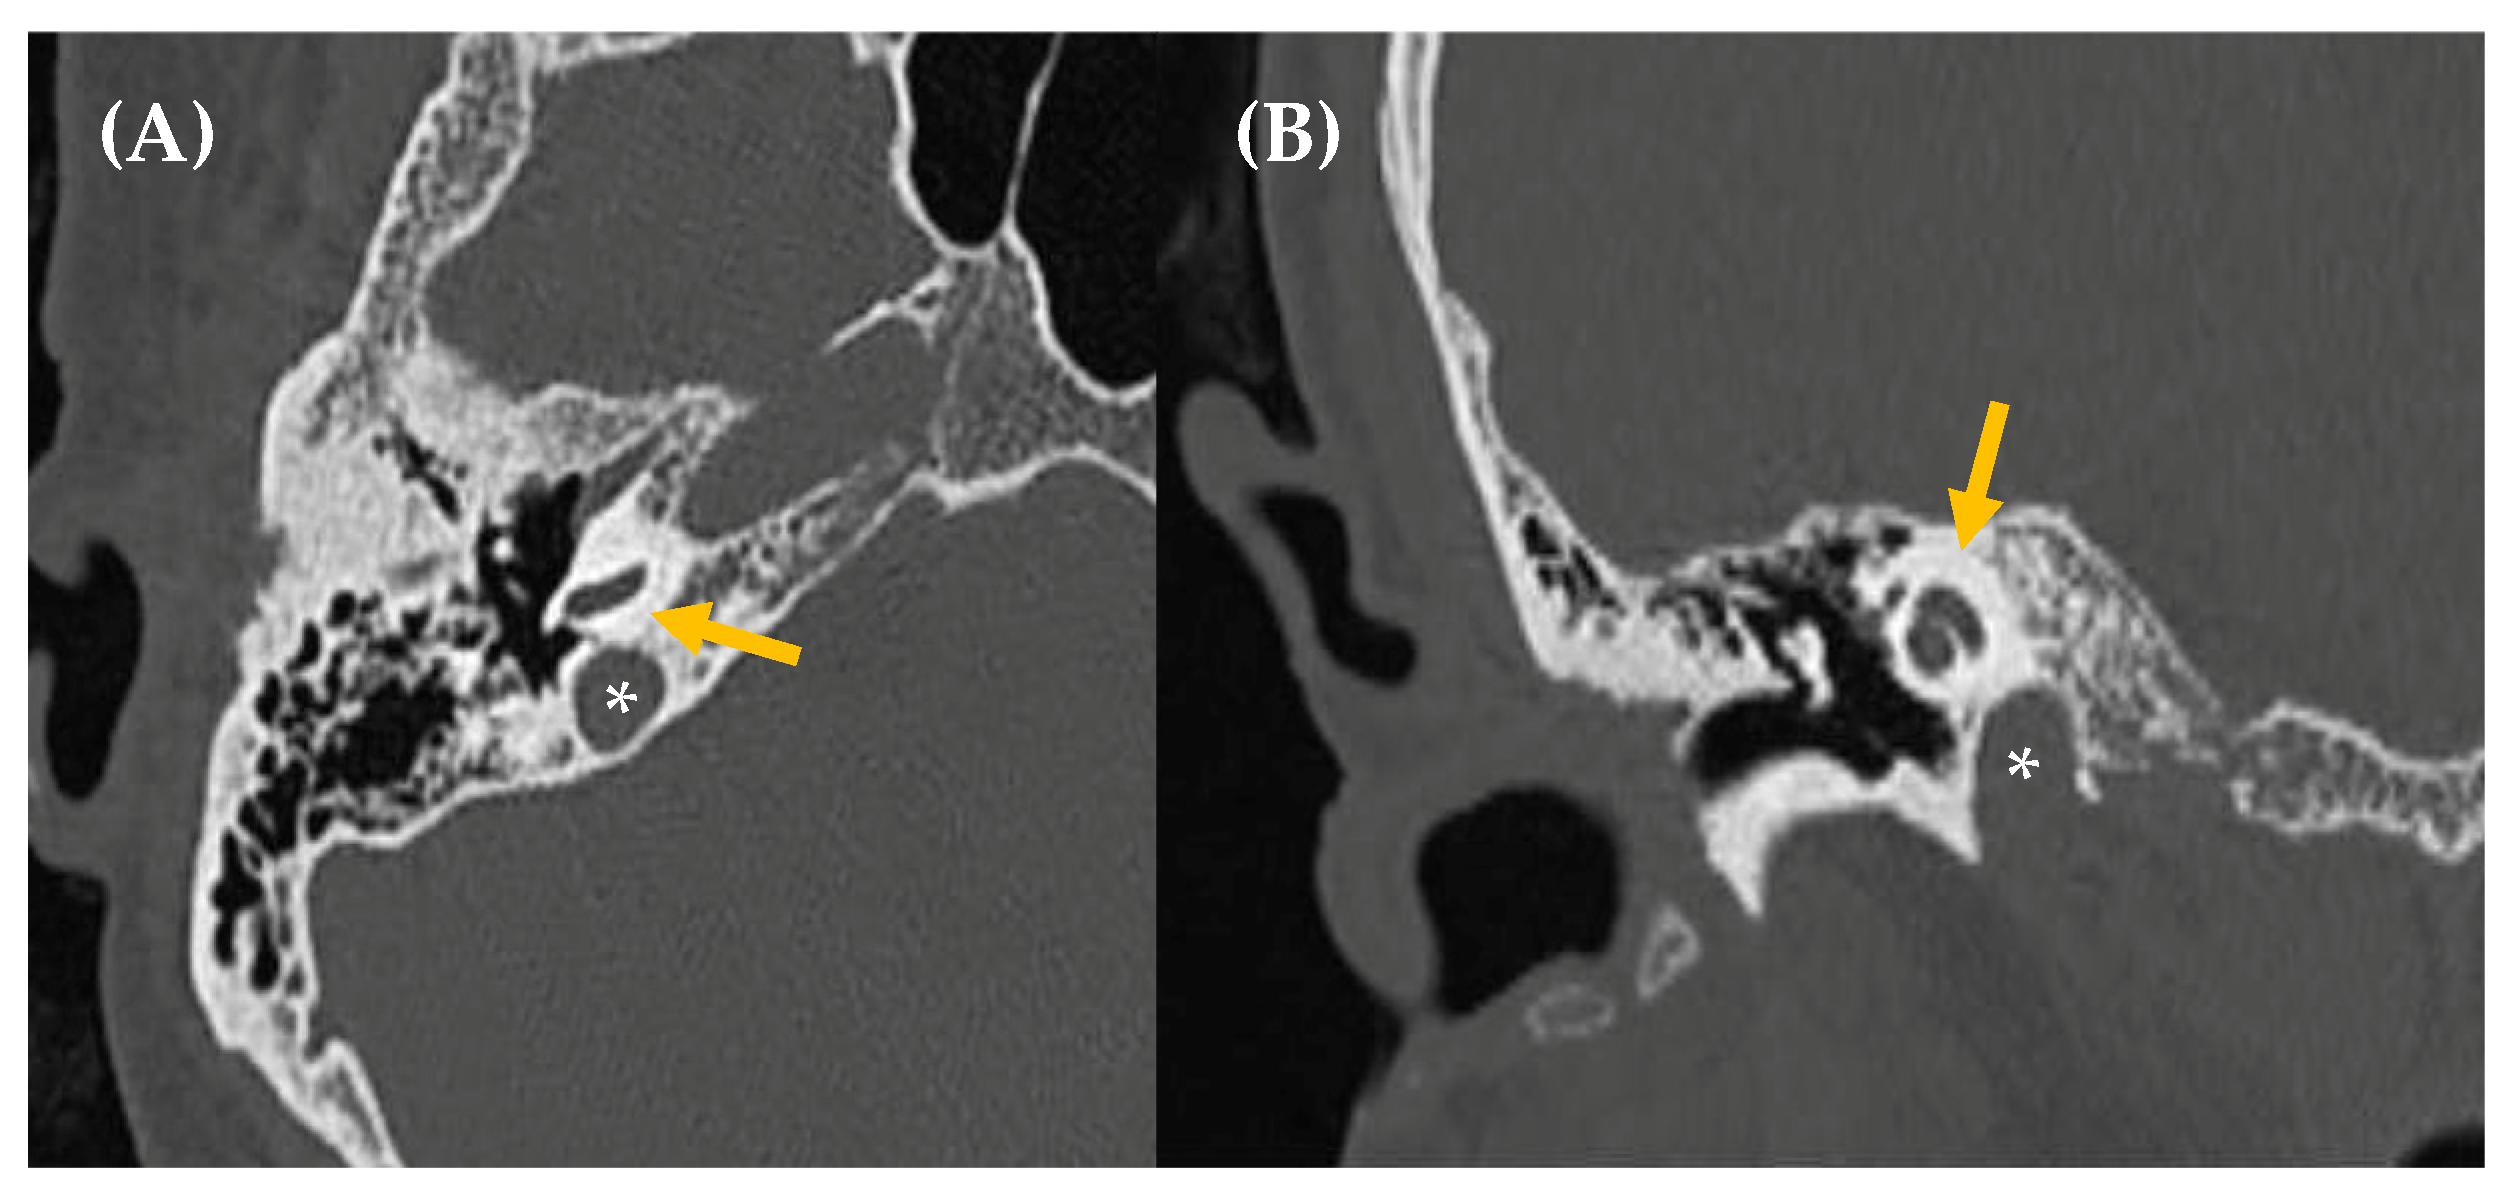

- High-riding/dehiscent jugular bulb

- Park, J.J.; Shen, A.; Loberg, C.; Westhofen, M. The relationship between jugular bulb position and jugular bulb related inner ear dehiscence: A retrospective analysis. Am. J. Otolaryngol. 2015, 36, 347–351. [Google Scholar] [CrossRef] [PubMed]

| Temporal bone abnormalities | Superior semicircular canal dehiscence Otosclerosis Paget’s disease Sigmoid sinus dehiscence/dehiscent jugular bulb Petrous carotid canal dehiscence |